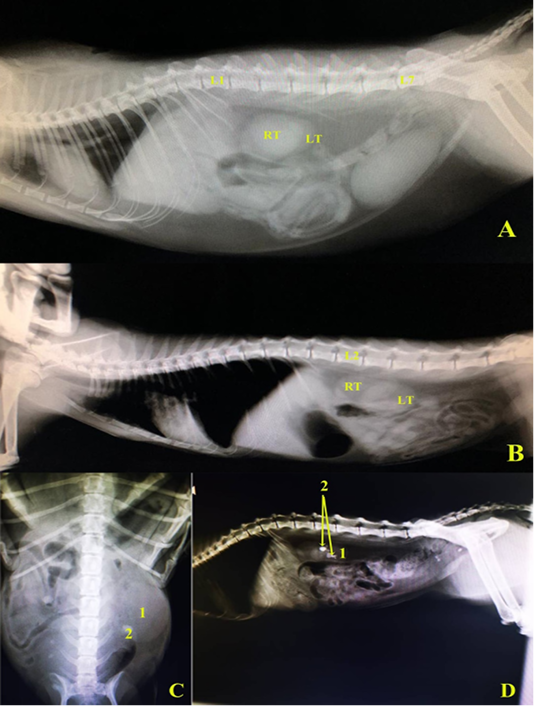

A and B, left lateral radiographic view in two domestic cats showing the normal positions of right and left kidneys. C, Ventrodorsal radiographic view showing enlarged left kidney (hydronephrosis), D, left lateral radiographic view showing renal calculi in left kidney, in domestic cats. L1.1st lumber vertebra, L2.2nd lumber vertebra, L7. 7th lumber vertebra, RT right kidney, LT.left kidney, 1 left kidney (hydronephrotic in C), 2. Renal calculus.